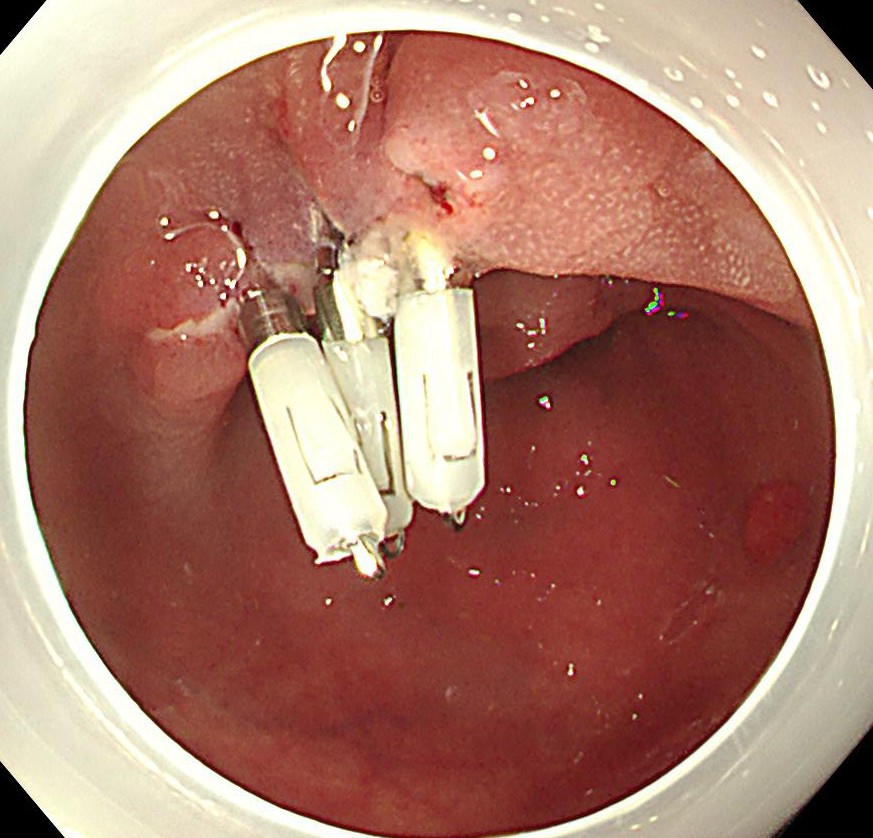

切除断端はクリップにて閉鎖します。